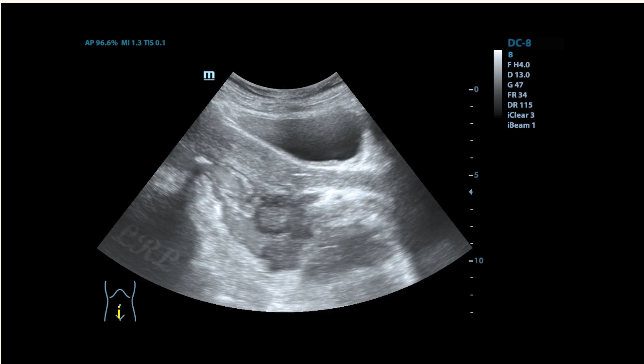

造影剂经直肠顺利通过,肠腔已无明显狭窄。

治疗7周后(2022-03-01日)超声示:

直肠壁仅可见一大小约2.1x1.0cm小低回声结节,其余结节及溃疡均已不显示。